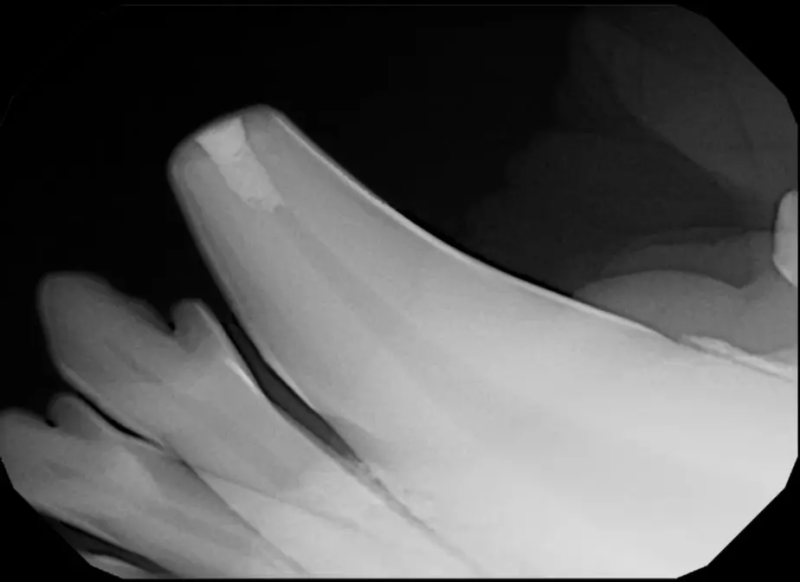

Root Canal Therapy

Root canal therapy is an excellent option for saving important teeth that have been fractured or are determined to be non-vital. The procedure is performed exactly as it would be for a human, except your pet will be dreaming peacefully under anesthesia. In many cases, root canal therapy is much easier on your pet than extraction, and preserves the structure of the tooth. It is important to have the root canal x-rayed periodically to monitor for any problems.